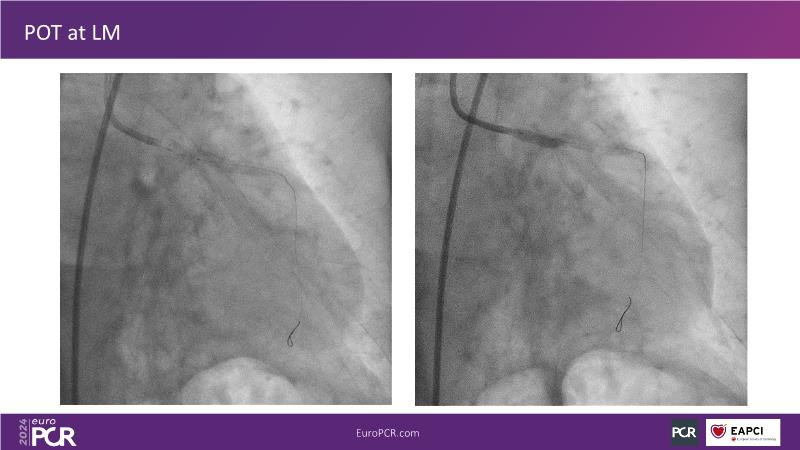

From innovation to reality: the impact of Cre8 EVO technology on complex PCI

This session is a good opportunity to delve into the contemporary technical and clinical complexities surrounding complex PCIs in challenging patient cases. Explore the necessary tools and treatment strategies to enhance peri-procedural and long-term clinical outcomes, and follow discussions on the unique technologies of Cre8 EVO in complex PCI scenarios.